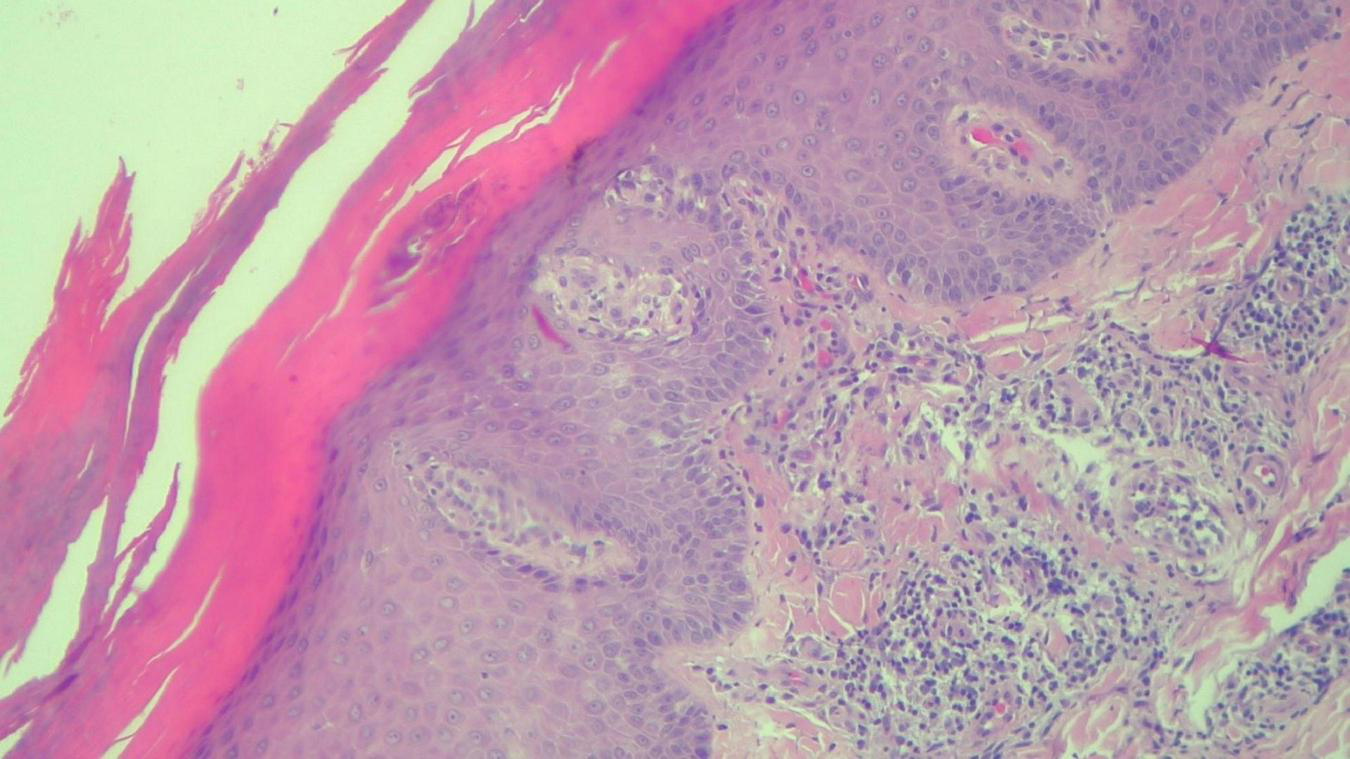

FIGURE 8

HEx100—Same patient with Munro microabcesses in the parakeratotic scale, focal agranulosis and more abundant inflammation in the superficial dermis.

The histopathological examination revealed (Figures 5–8). The examined skin fragment reveals an epidermis with marked hyperkeratosis, both ortho- and parakeratosis (confluent, with accumulations of neutrophils at this level—Munro microabscesses), a granular layer of variable thickness, with hypergranulosis and agranulosis, Kogoj pustules, regular psoriasiform acanthosis with elongated epidermal ridges, some rounded at the ends and fused at this level. The superficial dermis shows congested blood vessels, some with a tortuous appearance, and a perivascular inflammatory infiltrate consisting of lymphocytes, histiocytes, neutrophils (minimal), and extravasated red blood cells. Areas of erythrocyte exocytosis are also observed at the epidermal level.